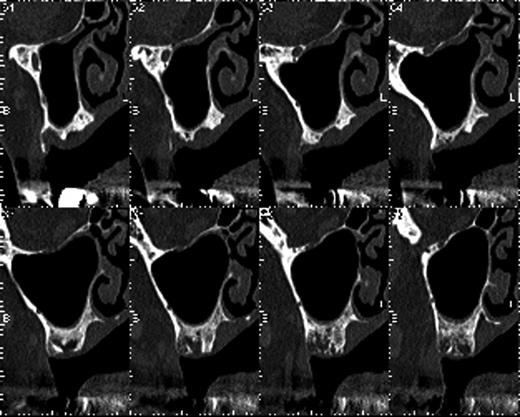

Preoperative orthopantomography. Molar teeth on the left side had been previously extracted because of severe periodontitis.

The patient used a jaw prosthesis with clasps over the remaining left maxillary teeth. However, these teeth were not strong enough to support a large jaw prosthesis that would cover the right maxillary defect, and residual teeth were missing. The patient sought implant treatment in the left maxillary molar region. However, computed tomography (CT) revealed that the bone mass of the left molar region was inadequate for implantation of these fixtures (Fig. 2). We performed the sinus-lift procedure under local anesthesia. The soft tissue from the canine region to the molar tooth region was incised and elevated to expose the underlying lateral wall of the left maxillary sinus. A 12 × 5 mm window was created in the bone of the maxillary sinus anterior wall with a piezoelectric instrument to expose the underlying Schneiderian membrane, which is the lining of the maxillary sinus cavity. Through careful instrumentation, the membrane was carefully peeled from the inner aspect of the sinus cavity (Fig. 3a). No damage to the membrane of the maxillary sinus was present. The newly formed space within the bony cavity of the sinus inferior to the intact membrane was grafted with artificial bone, and artificial bone was placed on the alveolar crest to raise the alveolar crest (Fig. 3b). The gingival flap was replaced and sutured to complete the sinus-lift procedure. There was minimal hemorrhage during the operation, and hemostasis was adequate. There was insignificant facial swelling immediately after the operation.

The bone mass in the left molar region was inadequate for implantation of fixtures.